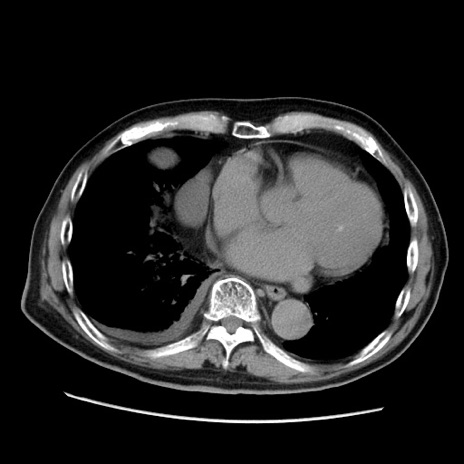

冠状断像

【症例】70歳代男性

【現病歴】肝硬変・肝細胞癌にてかかりつけの方。約9時間前に食後より腹痛出現。症状が徐々に増悪し、嘔吐出現したため来院。

【既往歴】肝硬変、肝細胞癌(RFA、TACE後)